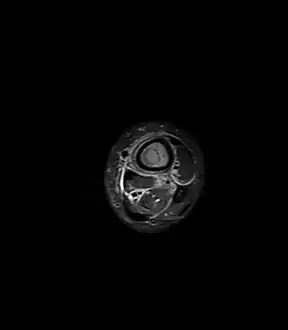

- Axial T1-weighted MRI pre-contrast enhancement showing that the intramedullary collection is T1-hyperintense suggesting proteinaceous viscous fluid consistent with infection.

- Axial T1-weighted fat-saturated MRI image following IV gadolinium contrast demonstrating the intramedullary lytic area seen on radiography to be ring enhancing consistent with a purulent fluid collection. Extensive circumferential periosteal enhancement is noted. There is also substantial bone marrow enhancement.